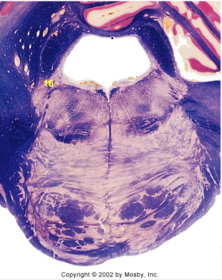

| Nucleus gracilis | |

| Accessory nucleus | |

| Medial longitudinal faciculus | |

| Pyramidal decussation | |

| Medullary pyramids | |

| Anterior spinocerebellar tract | |

| ALS | |

| Posterior spinocerebellar tract | |

| Spinal tract of V | |

| Spinal nucleus of V | |

| Nucleus cuneatus | |

| Fasciculus cuneatus | |

| Fasciculus gracilis | |

| Central canal | |

| Internal acruate fibers | |

| Lateral (external/accessory) cuneate nucleus | |